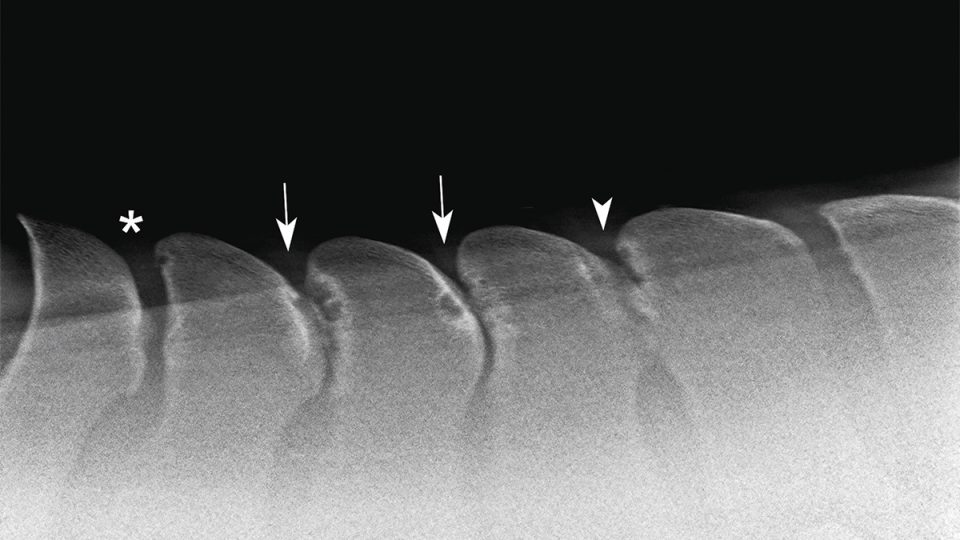

El término kissing spines se refiere a una patología denominada médicamente procesos espinosos dorsales sobrepuestos(Overriding Dorsal Spinous Processes, ORDSP).

Se produce cuando las apófisis espinosas de las vértebras dorsales (habitualmente entre la T13 y la T18) se aproximan demasiado o llegan a tocarse.

En los casos más severos, incluso rozan entre sí, provocando inflamación, dolor y contractura muscular.

Las radiografías son fundamentales para confirmar el diagnóstico, pero no siempre cuentan toda la historia.

Algunos caballos con imágenes muy marcadas no muestran síntomas, mientras que otros con hallazgos leves sí presentan molestias severas.